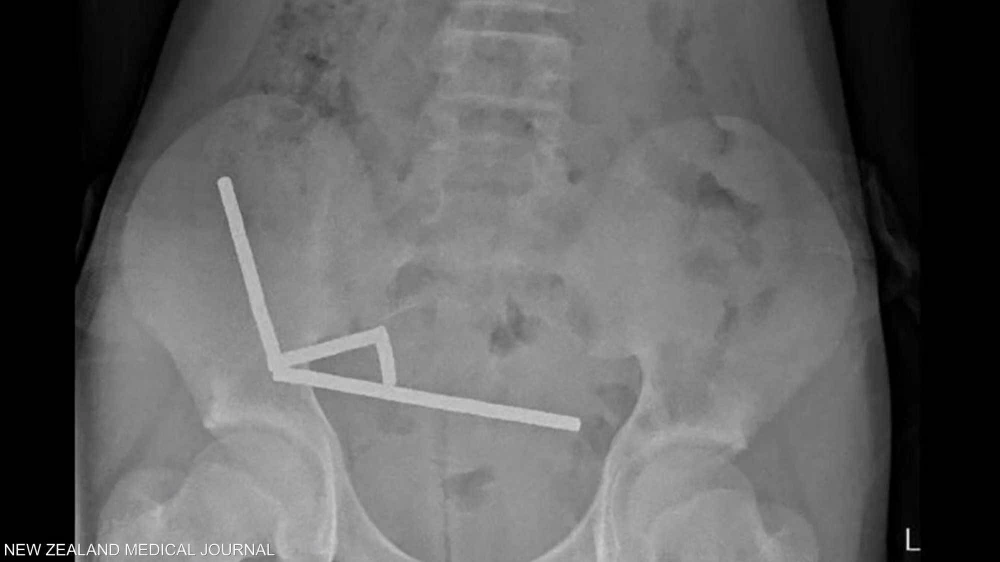

صبي في نيوزيلندا يبتلع 100 مغناطيس اشتراها من «تيمو».. والشركة تعلق

ابتلع صبي عمره 13 عاما نحو 100 مغناطيس اشتراه عبر الإنترنت، مما أجبر الجراحين في نيوزيلندا على إزالة أنسجة تالفة من أمعائه. وبعد معاناته آلاما في البطن استمرت 4 أيام، نقل المراهق، الذي لم يكشف عن اسمه، إلى مستشفى تاورانغا في الجزيرة الشمالية لنيوزيلندا. وجاء في تقرير صادر عن أطباء المستشفى في المجلة الطبية النيوزيلندية: "أكد أنه...